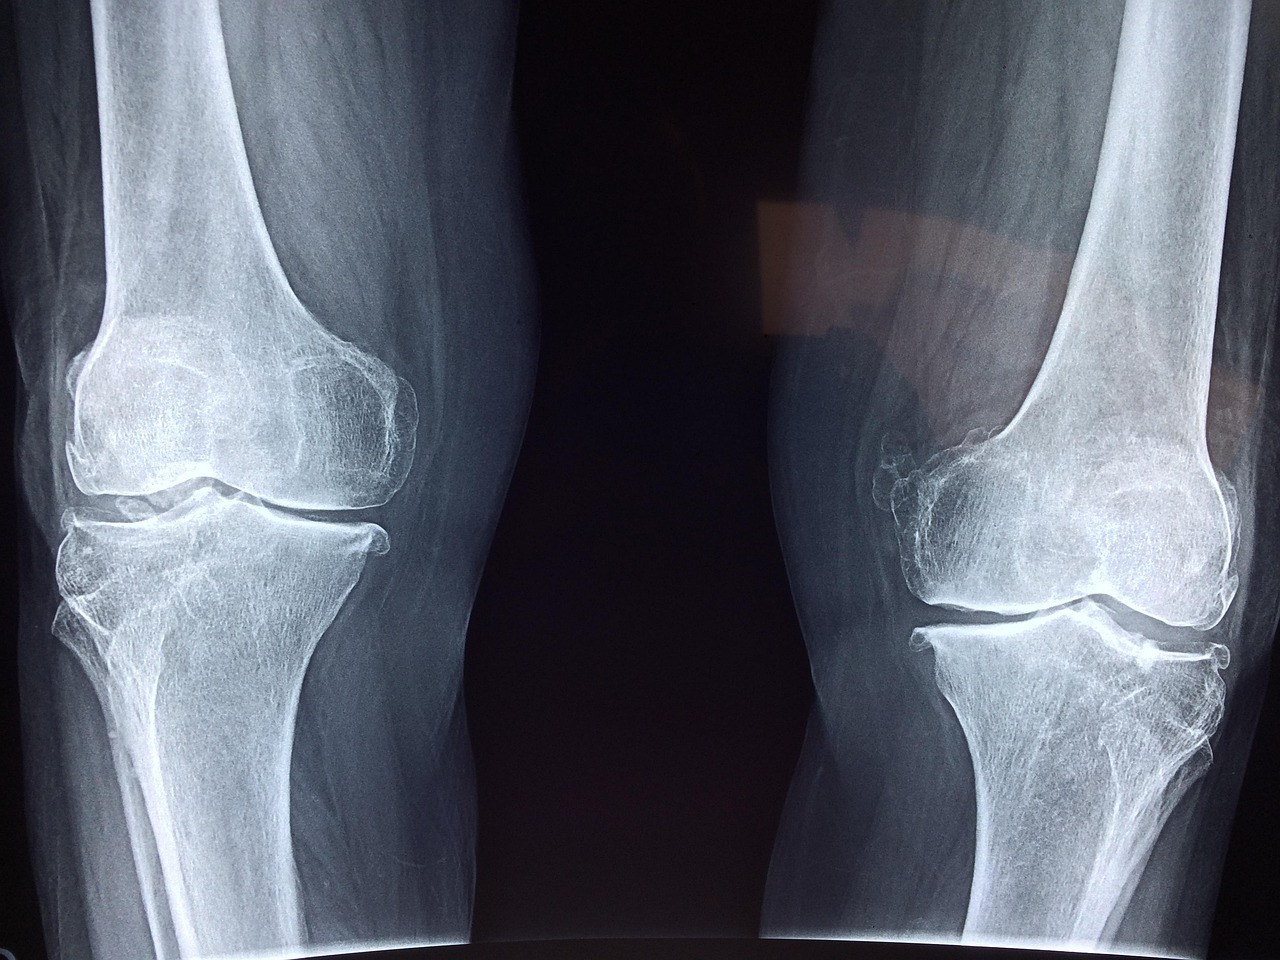

인공관절 수술 성공을 위한 3가지 체크포인트

인공관절은 나이와 무관하게 관절 통증과 기능 저하를 겪는 많은 이들에게 큰 희망이 됩니다. 특히 인공관절전문병원은 최신 의료기술과 숙련된 의료진이 모여 최적의 치료를 제공하는 곳입니다. 이곳에서는 맞춤형 수술과 회복 프로그램을 통해 빠른 일상 복귀를 도와줍니다. 오늘은 인공관절전문병원에 대해 자세히 알아보도록 하겠습니다! 자주 묻는 질문 (FAQ) 📖 Q: 인공관절 수술 후 회복 기간은 얼마나 걸리나요? A: 인공관절 … Read more